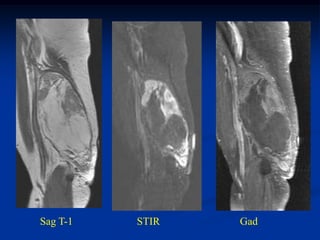

Case #283.1      Well Differentiated Liposarcoma Thigh

Cor T-1         STIR                     Gad

68 yr old male with three time recurrence of soft mass in thigh

Axial T-1   STIR

Gad